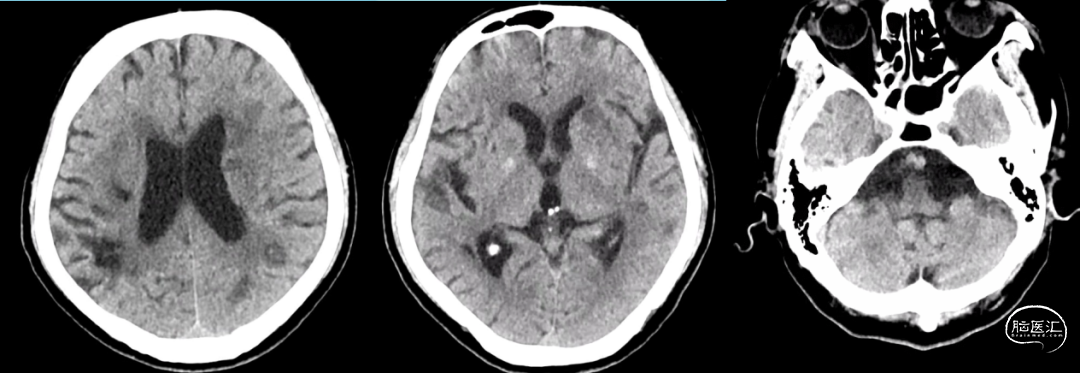

急查头颅CT+CTA检查示:左侧基底节区及放射冠区腔隙性脑梗塞、双侧颈内动脉及基底动脉硬化、左侧大脑中动脉M1段以远闭塞。予阿替普酶58.5mg静脉溶栓治疗,溶栓治疗后患者症状未见明显改善,经我科急会诊后拟“急性大脑中动脉闭塞脑梗死” 收住入院,患者自起病以来,呈嗜睡状态,胃纳一般,大小便如常,近期体重无明显变化。

术前头颅CT+CTA:左侧基底节区及放射冠区腔隙性脑梗塞、双侧颈内动脉及基底动脉硬化、左侧大脑中动脉M1段以远闭塞。

左侧大脑中动脉M1段闭塞。

前、后交通动脉均未开放,未见后循环经软脑膜支代偿血运供应左侧颞叶。